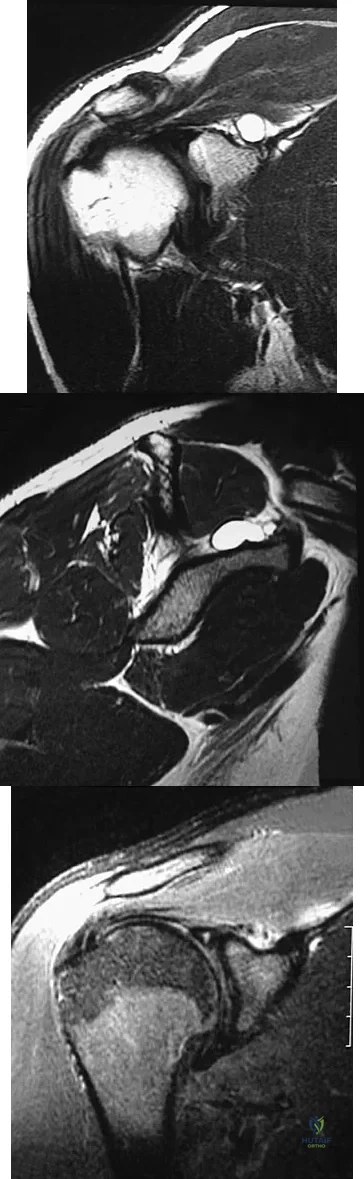

A 40-year-old man reports an enlarging soft-tissue mass in his right shoulder. Based on the MRI scan and biopsy specimens shown in Figures 40a through 40c, what is the most likely diagnosis?

Explanation

A 28-year-old woman has left shoulder pain and a tender soft-tissue mass. Based on the MRI scan and biopsy specimens shown in Figures 74a through 74c, what is the most likely diagnosis?

Explanation